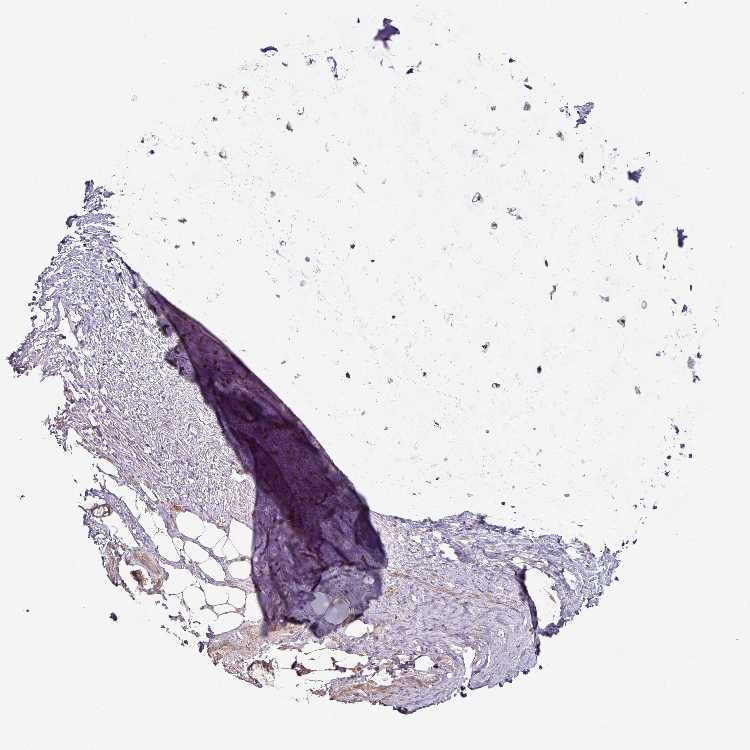

SOFT TISSUE 1 - Antibody stainingi

Antibody staining in the annotated cell types in the current human tissue is reported as not detected, low, medium, or high, based on conventional immunohistochemistry profiling in selected tissues. This score is based on the combination of the staining intensity and fraction of stained cells.

Each image is clickable and will lead to virtual microscopy that enables deeper exploration of all samples and also displays staining intensity scores, fraction scores and subcellular localization as well as patient and tissue information for each sample.

Antibody HPA023015Antibody HPA052395

Chondrocytes -Medium

Fibroblasts MediumLow

Peripheral nerve Low-